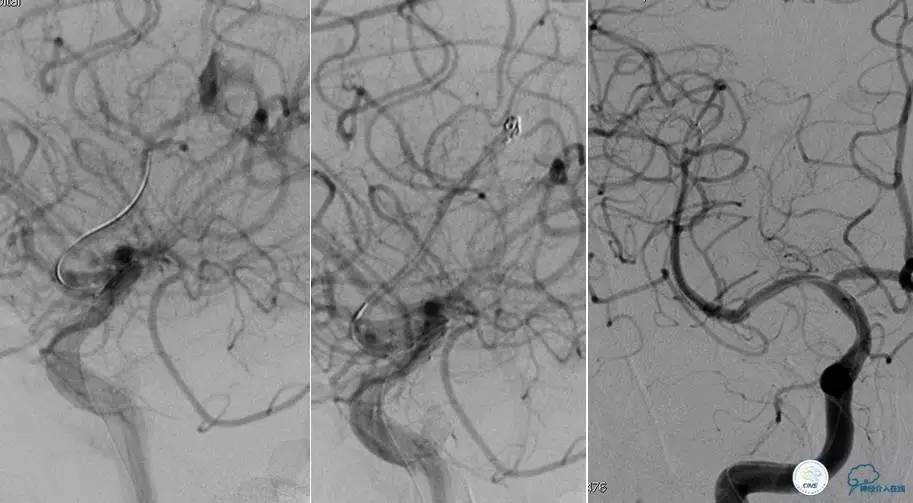

半年后复查造影,无支架内再狭窄,可见弹簧圈,患者恢复至自己柱杖行走。

患者:49岁女性,脑梗死30天。

左侧颈内动脉末端闭塞,末端圆钝且有一定成角,开通难度较大,多次尝试导丝才成功穿过闭塞段。

开通效果很满意,术后症状明显恢复。